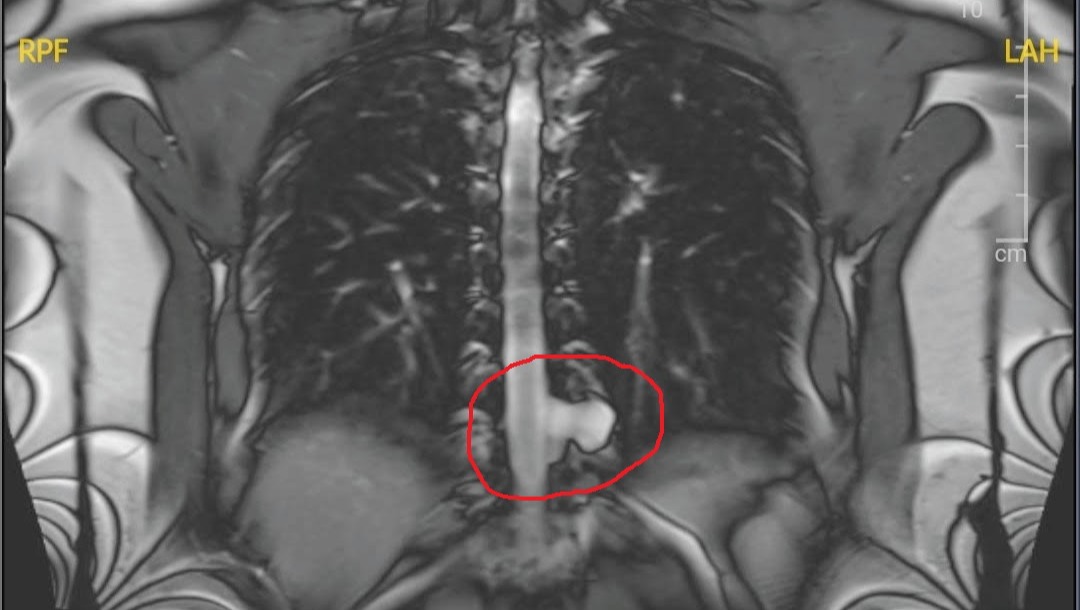

If you know Anca, you know that she is endlessly generous, selfless, and optimistic. It has been very difficult and impressive to watch her struggle for the past few years, working hard to care for sick family members while still somehow maintaining her high standard of patient care. She has also accrued significant debt in the process. After nursing family back to health, she has encountered her own web of confusing and debilitating medical conditions which have been challenging to diagnose. The most urgent of these is a cerebrospinal fluid leak which is inhibiting her from living her life to any meaningful degree. Fortunately, she has been approved to see a surgeon in California who will be able to operate on her leak. Unfortunately, her disability has prevented her from working an adequate number of hours and her medical debt will only continue to grow. It remains unknown if insurance will cover her surgery and associated procedures/diagnostics, or to what degree. Any amount is helpful, no matter how small, even a penny and well wishes :-)

Below is an image of Anca's CSF leak: